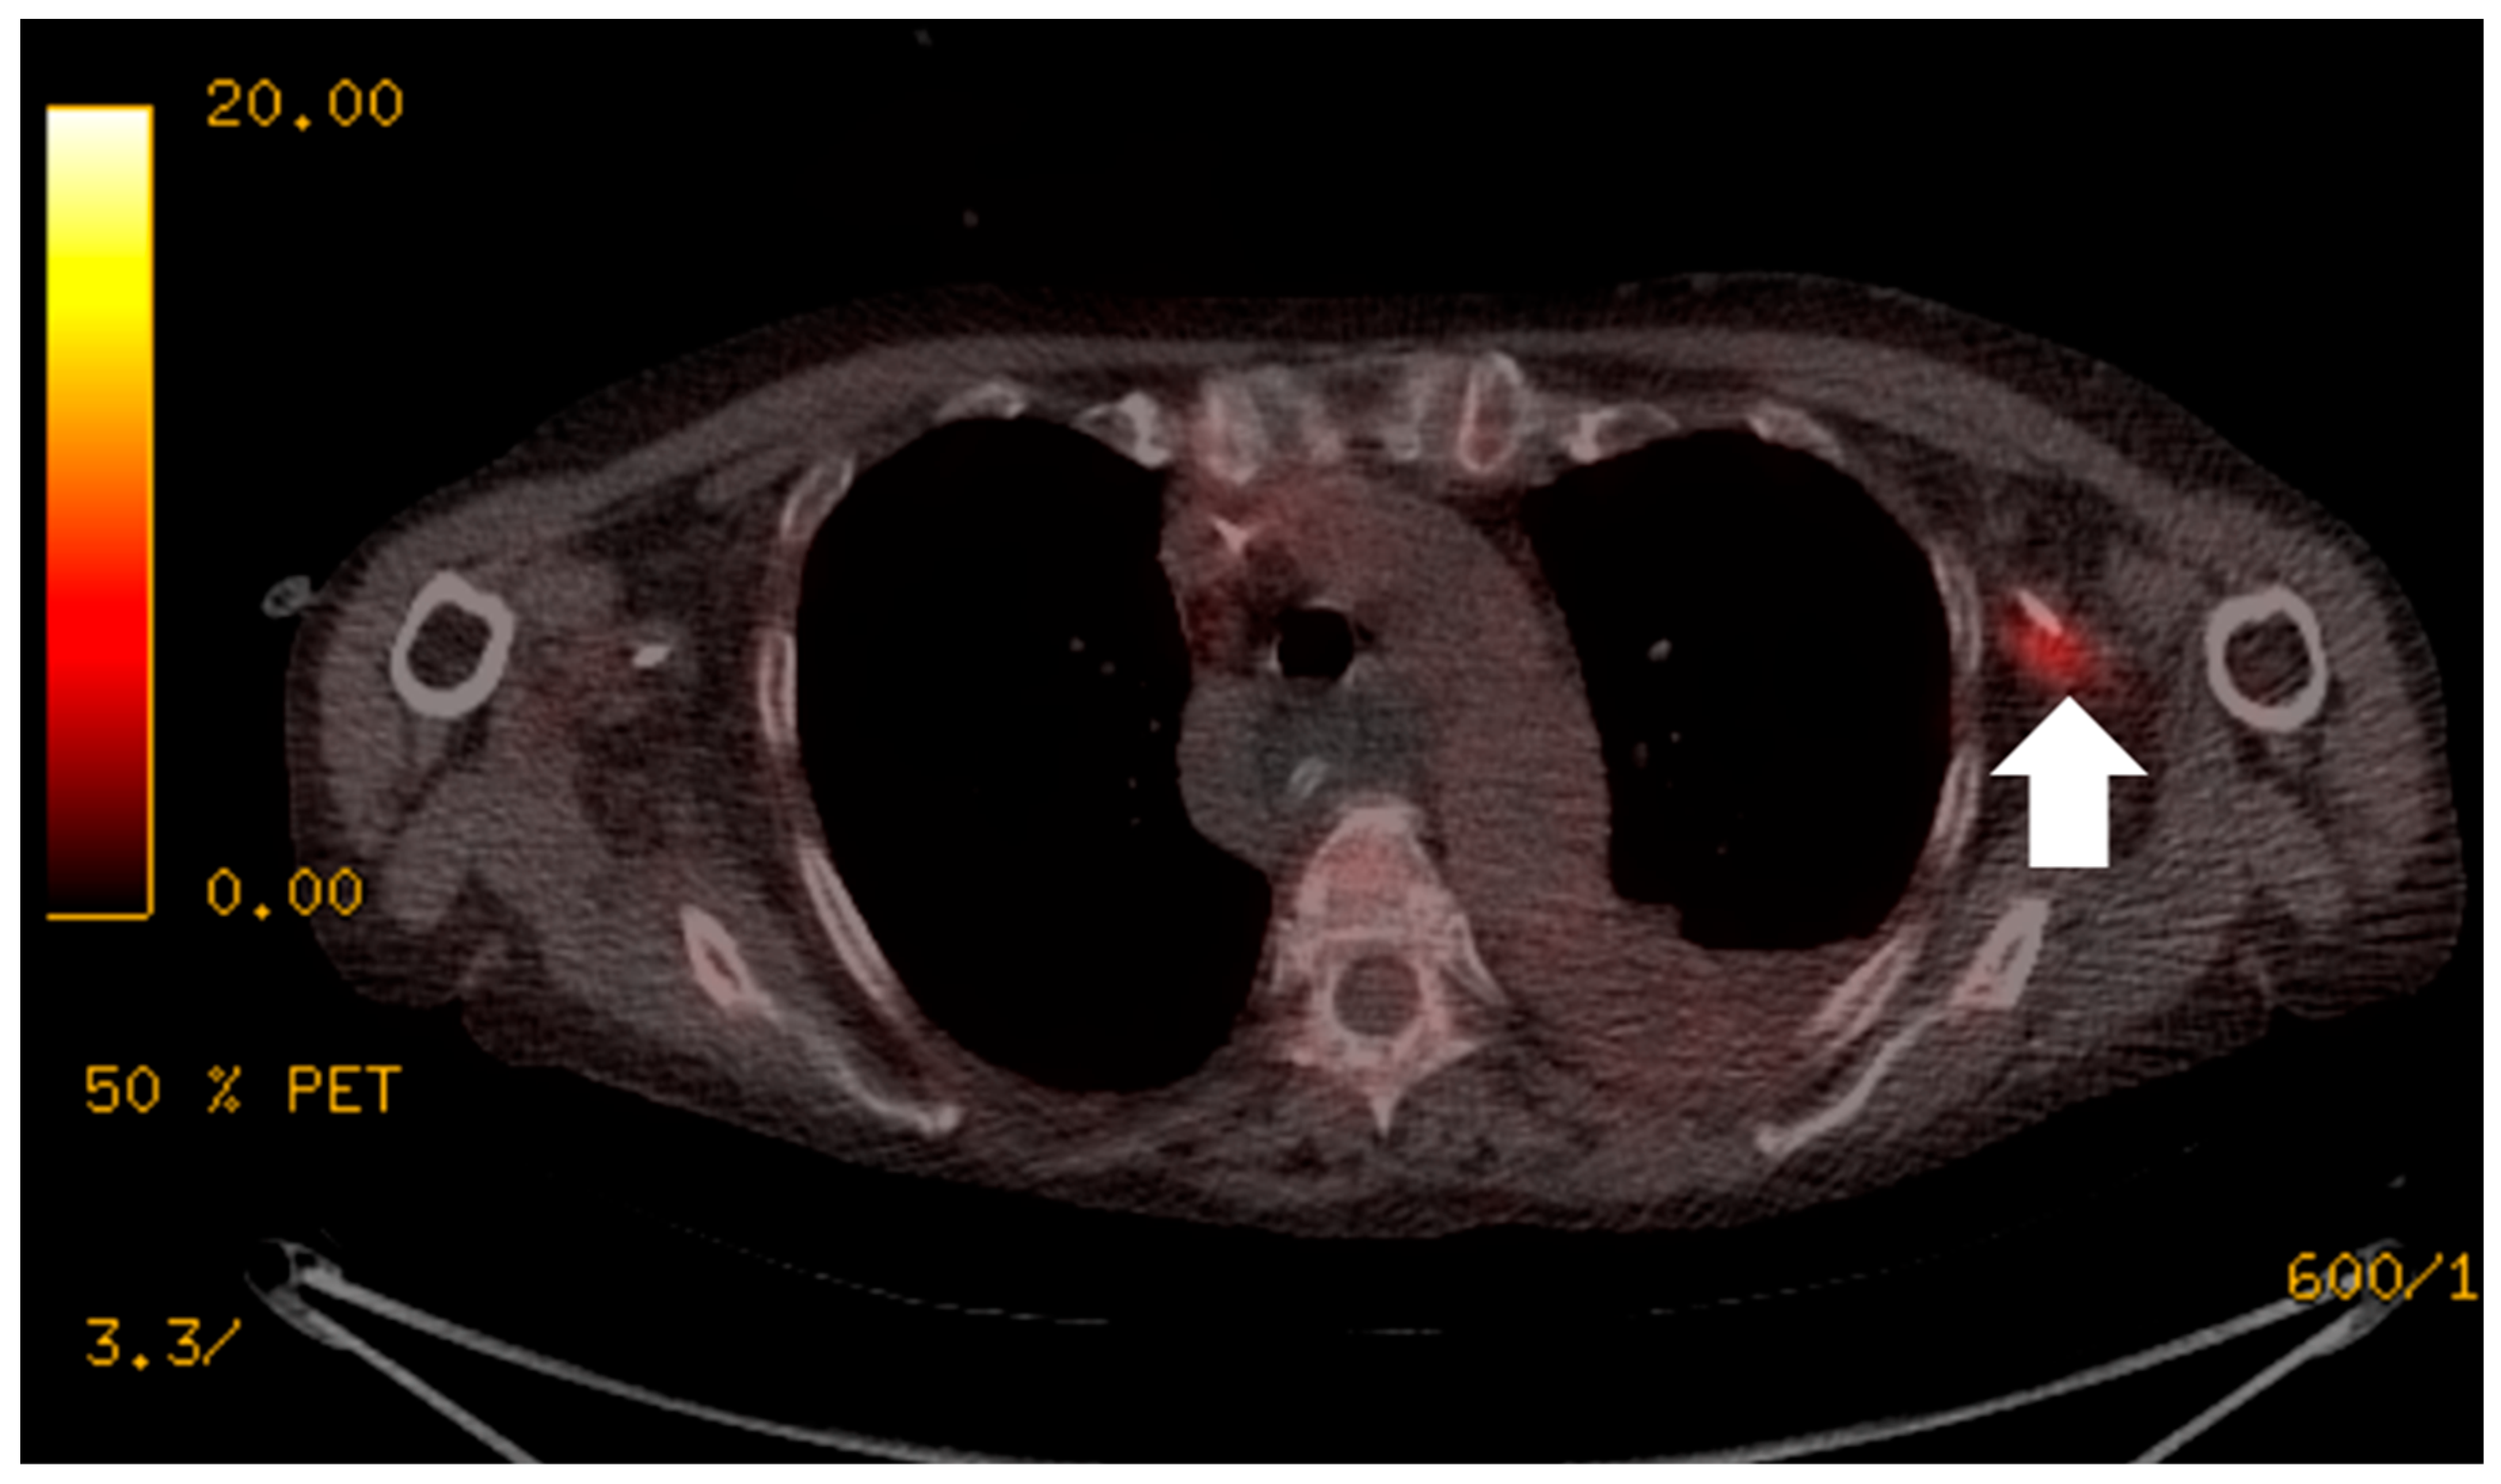

Figure 3. The patient presented with continued pyrexia and a white cell count of 40 × 109cells/L. CT from 4 days prior demonstrated a lesser sac collection (A) with clinical concerns that the lesser sac collection (white arrows, image (A)) may be the source of sepsis and the permacol gusset mesh used for closure may be infected. 18F-FDG PET/CT (B,C) demonstrated the collection in the lesser sac (white arrows, image (B)) is likely to be innocuous as it did not show high tracer uptake and there was no significant uptake at the site of the permacol gusset closure material (short arrows, image (C)) to suggest an infected implant. The patient avoided a repeat operation for a surgical washout of the lesser sac collection and the removal of the closure mesh.